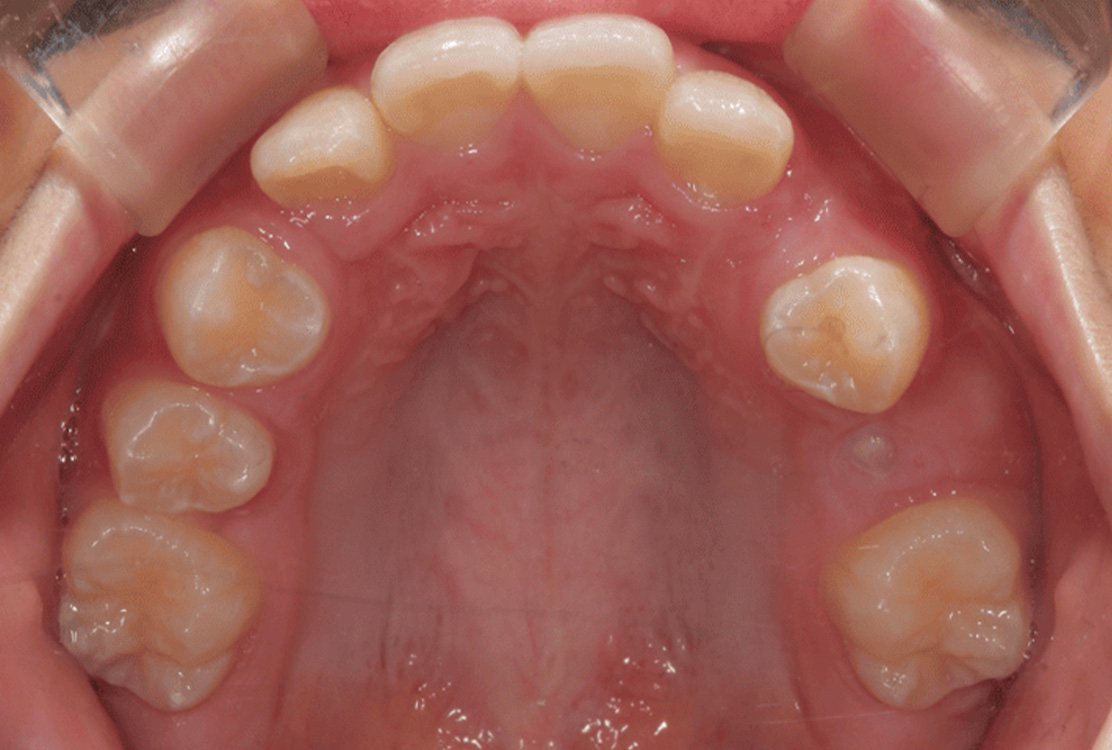

治療前